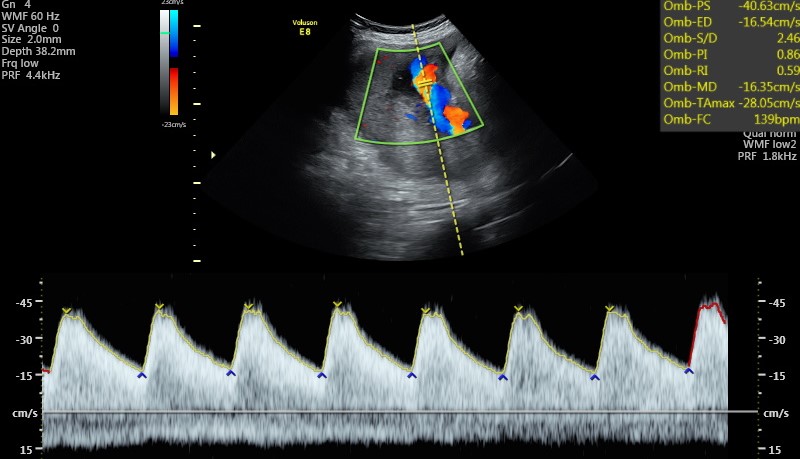

Nel caso che il tesoro, nelle ecografie precedenti, sia risultato un po’ sovrappeso o un po’ sottopeso, sarebbe meglio eseguire una ulteriore valutazione della crescita fetale e del benessere fetale fra la fine dell’ottavo o l’inizio del nono mese.